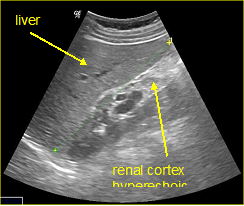

In a 4-years period (from 2016 to 2019) a retrospective study of 887 patients with fatty infiltration of the liver was performed, out of which 608 were males and 272 were females, aged 42 to 69 and 7 obese children (age from 8 to 13 years). All patients were examined in the ultrasound cabinet of our hospital (hospitalized, regular appointments and emergency incidents) and subjected to upper abdominal ultrasound scan, with convex transducer 4C MHz, in three ultrasound imaging planes: transverse, oblique and sagittal planes.5−7 In order to better depict the liver, especially in obese patients or those with excessive intestinal gas, the patients were asked to inhale deeply and hold their breath for the duration of the ultrasonographic examination for a few seconds at a time, so that the liver could be visible in its entirety. The ultrasound examination revealed the echogenicity of the parenchyma of the liver and was compared with the parenchyma of the right kidney, the spleen and the pancreas (Figure 1−3). Τhere is always the risk of missing a diagnosis of mild hepatic steatosis on ultrasound if there is concurrent chronic renal disease, which increases the echogenicity of the kidneys (Figure 4), if there is any doubt that the patient might have a chronic renal disease, comparison of the liver to the left kidney and the spleen may be useful.8

Figure 1 Right renal cortex appearing hypoechoic compared to the liver parenchyma.